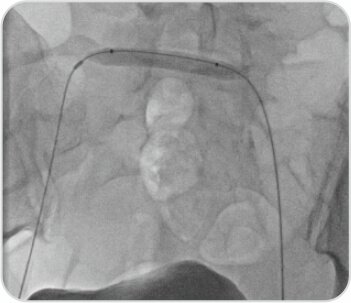

Lesion was very difficult to cross, multiple attempts made, (long sheath, Vert catheter, Rubicon catheter) finally Terumo wire could be negotiated into Rt CIV. Wire snared from Rt. CFV.

F/B 7 ×40 mm (Conquest PTA balloon)

was crossed, predilatation done. Tight Lesion

Venoplasty with , multiple balloon dilatation were done starting by 2.5×80 mm. PTA balloon Sheath in left groin changed to 11F , 12 × 40 mmAtlasPTAballoonat24atm.Adequate Dilatation at bifurcation into IVCA post-angioplasty venogram demonstrated a widely patent stent and good contrast flow through the stent into the inferior vena cava, without filling of the cross-pelvic collaterals.